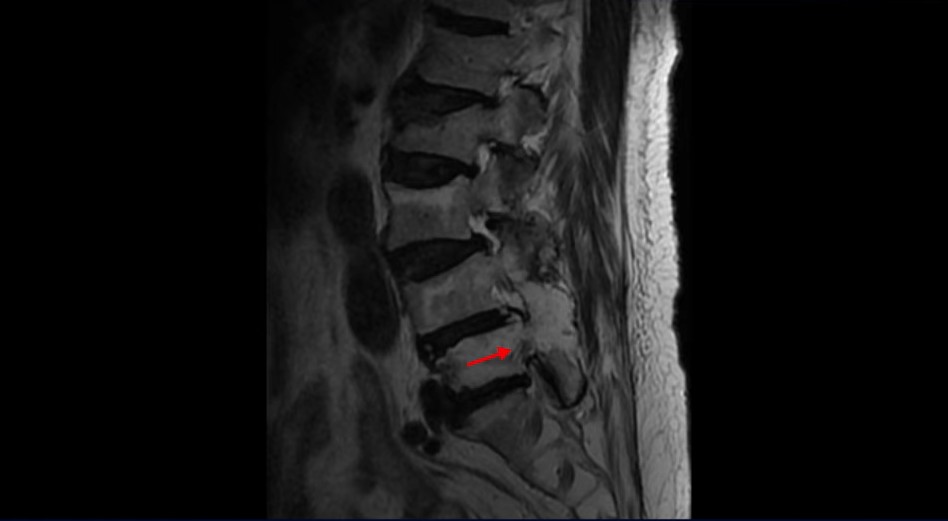

이 환자분은 협착증 수술 예약을 날짜까지 잡아놓고 넘어지면서 압박골절이 발생하고 협착증 증상 즉, 골반과 다리증상이 심하게 악화됩니다. 이분 MRI를 보시면 척추 2번 뼈에는 넘어지면서 생긴 척추압박골절이 보입니다.

3번과 4번 마디에는 황색인대 골화증으로 인한 중심성 협착이 보입니다.

4번과 5번 마디는 전방전위증이 있고 15년 전 허리수술을 받은 적이 있어서 척추 후관절과 후궁을 제거한 흔적들이 보입니다.

또 5번 1번에는 왼쪽 신경가지가 빠져나가는 추간공 즉 신경구멍이 많이 좁아져 있습니다. 이 환자분은 허리통증과 함께 왼쪽 다리 증상이 심하셨는데 이것 때문인 것으로 보입니다.